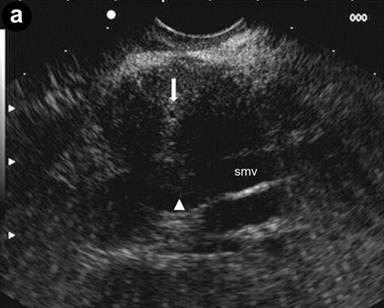

A 36-year-old man with jaundice and mild abdominal pain. Computed tomography (CT) showed dilated intra- and extra-hepatic bile ducts with diffuse pancreatic swelling. EUS linear scanning (Image 2a) showed an enlarged pancreatic head with an irregular hypoechoic lesion, loss of interface (arrowhead) with the superior mesenteric vein (smv), and a normal main pancreatic duct (arrow). The remaining pancreas (Image 2b) was also diffusely enlarged with hypoechoic echotexture and hyperechoic septa. The patient responded to steroid therapy.